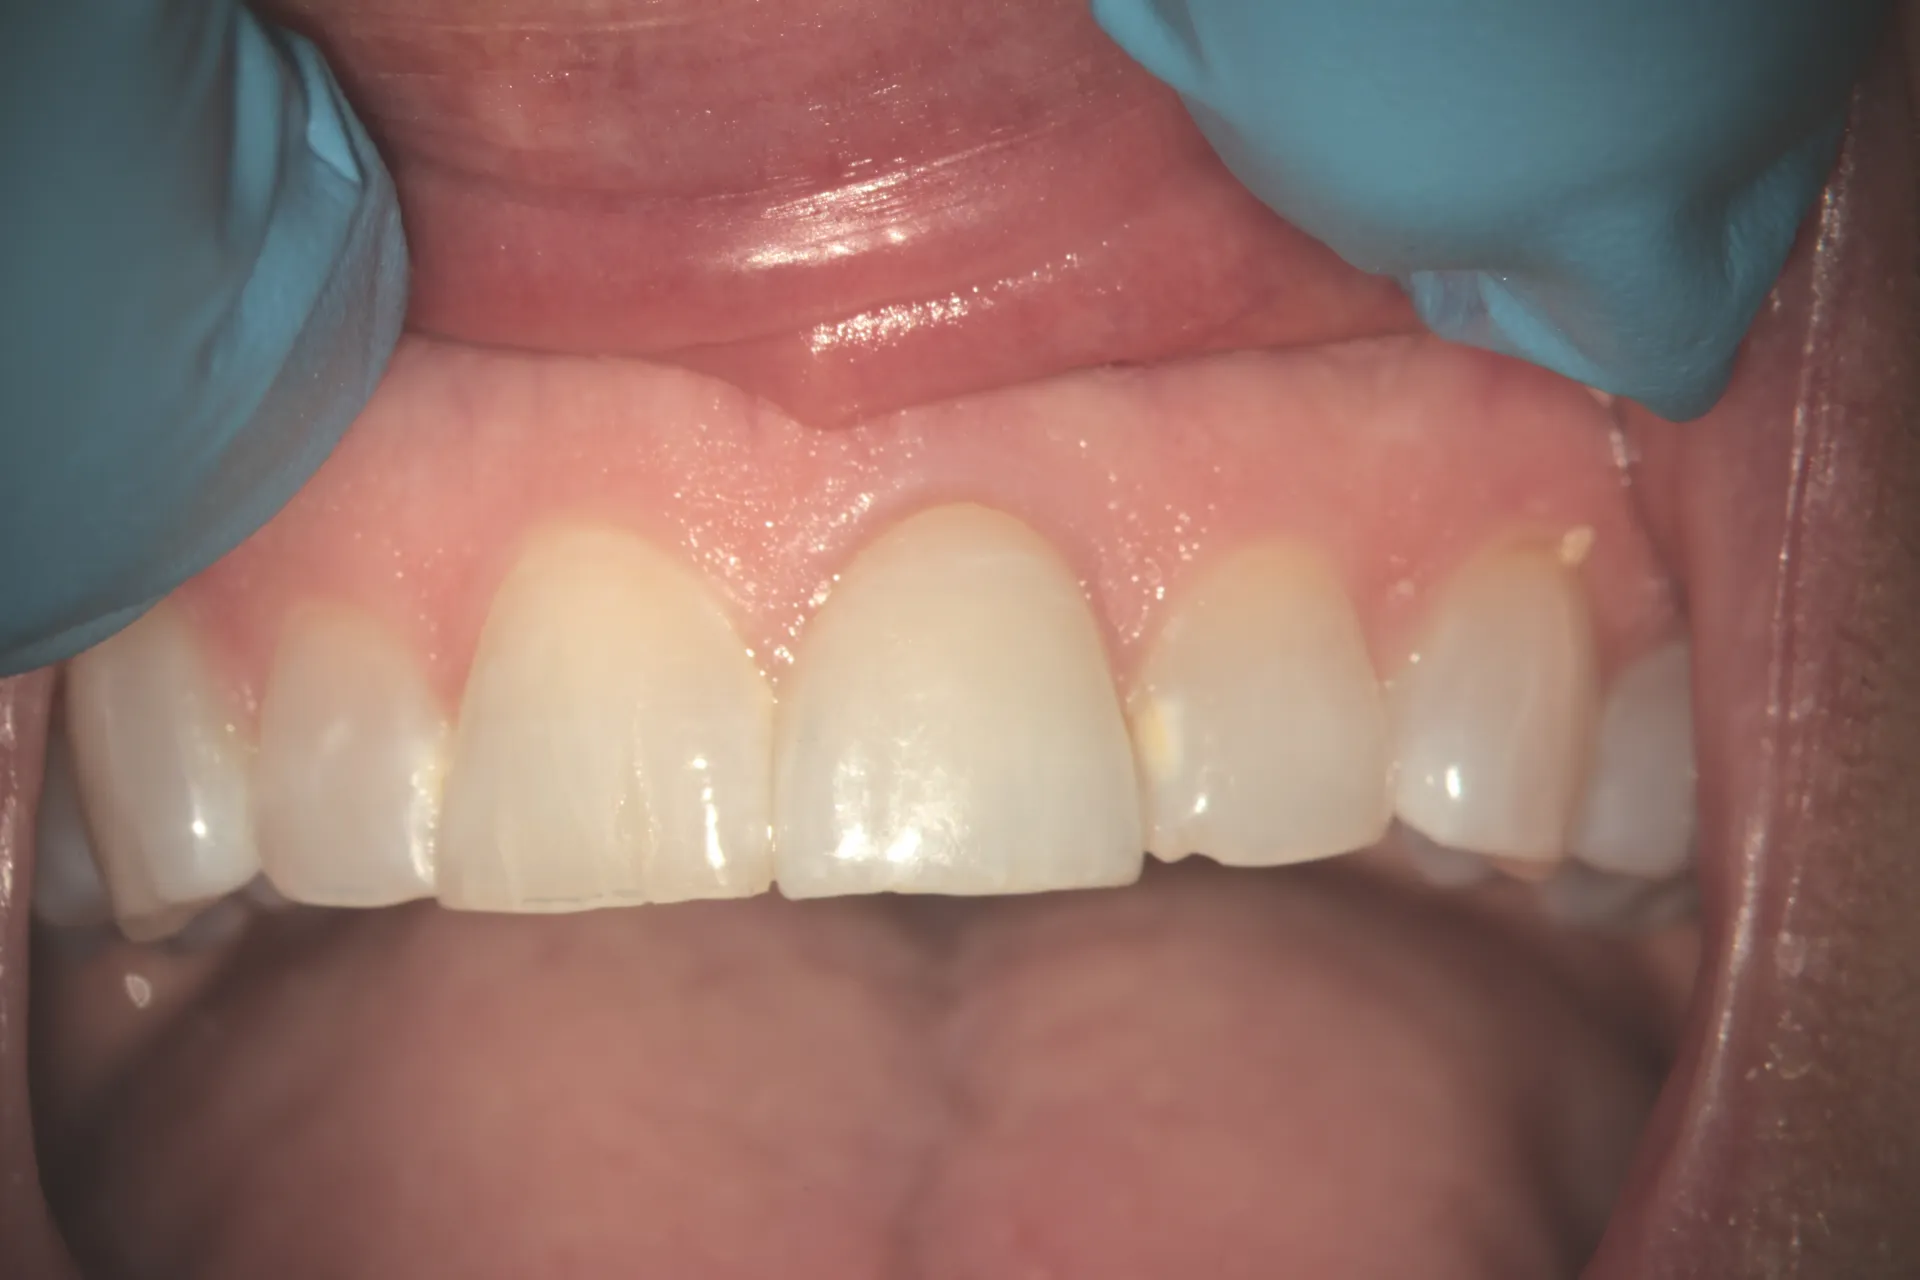

This Case at 1-Year Follow-Up

At one-year recall, the tooth demonstrated:

• Asymptomatic function: No pain, sensitivity, or discomfort

• Radiographic success: No periapical radiolucency, stable bone levels

• Intact restoration: Full coverage crown showing no signs of failure

• Normal mobility: Physiologic mobility consistent with healthy periodontal ligament

• Patient satisfaction: Highly satisfied with decision to save natural tooth

• Aesthetic success: Tooth matches adjacent central incisor in color, contour, and translucency